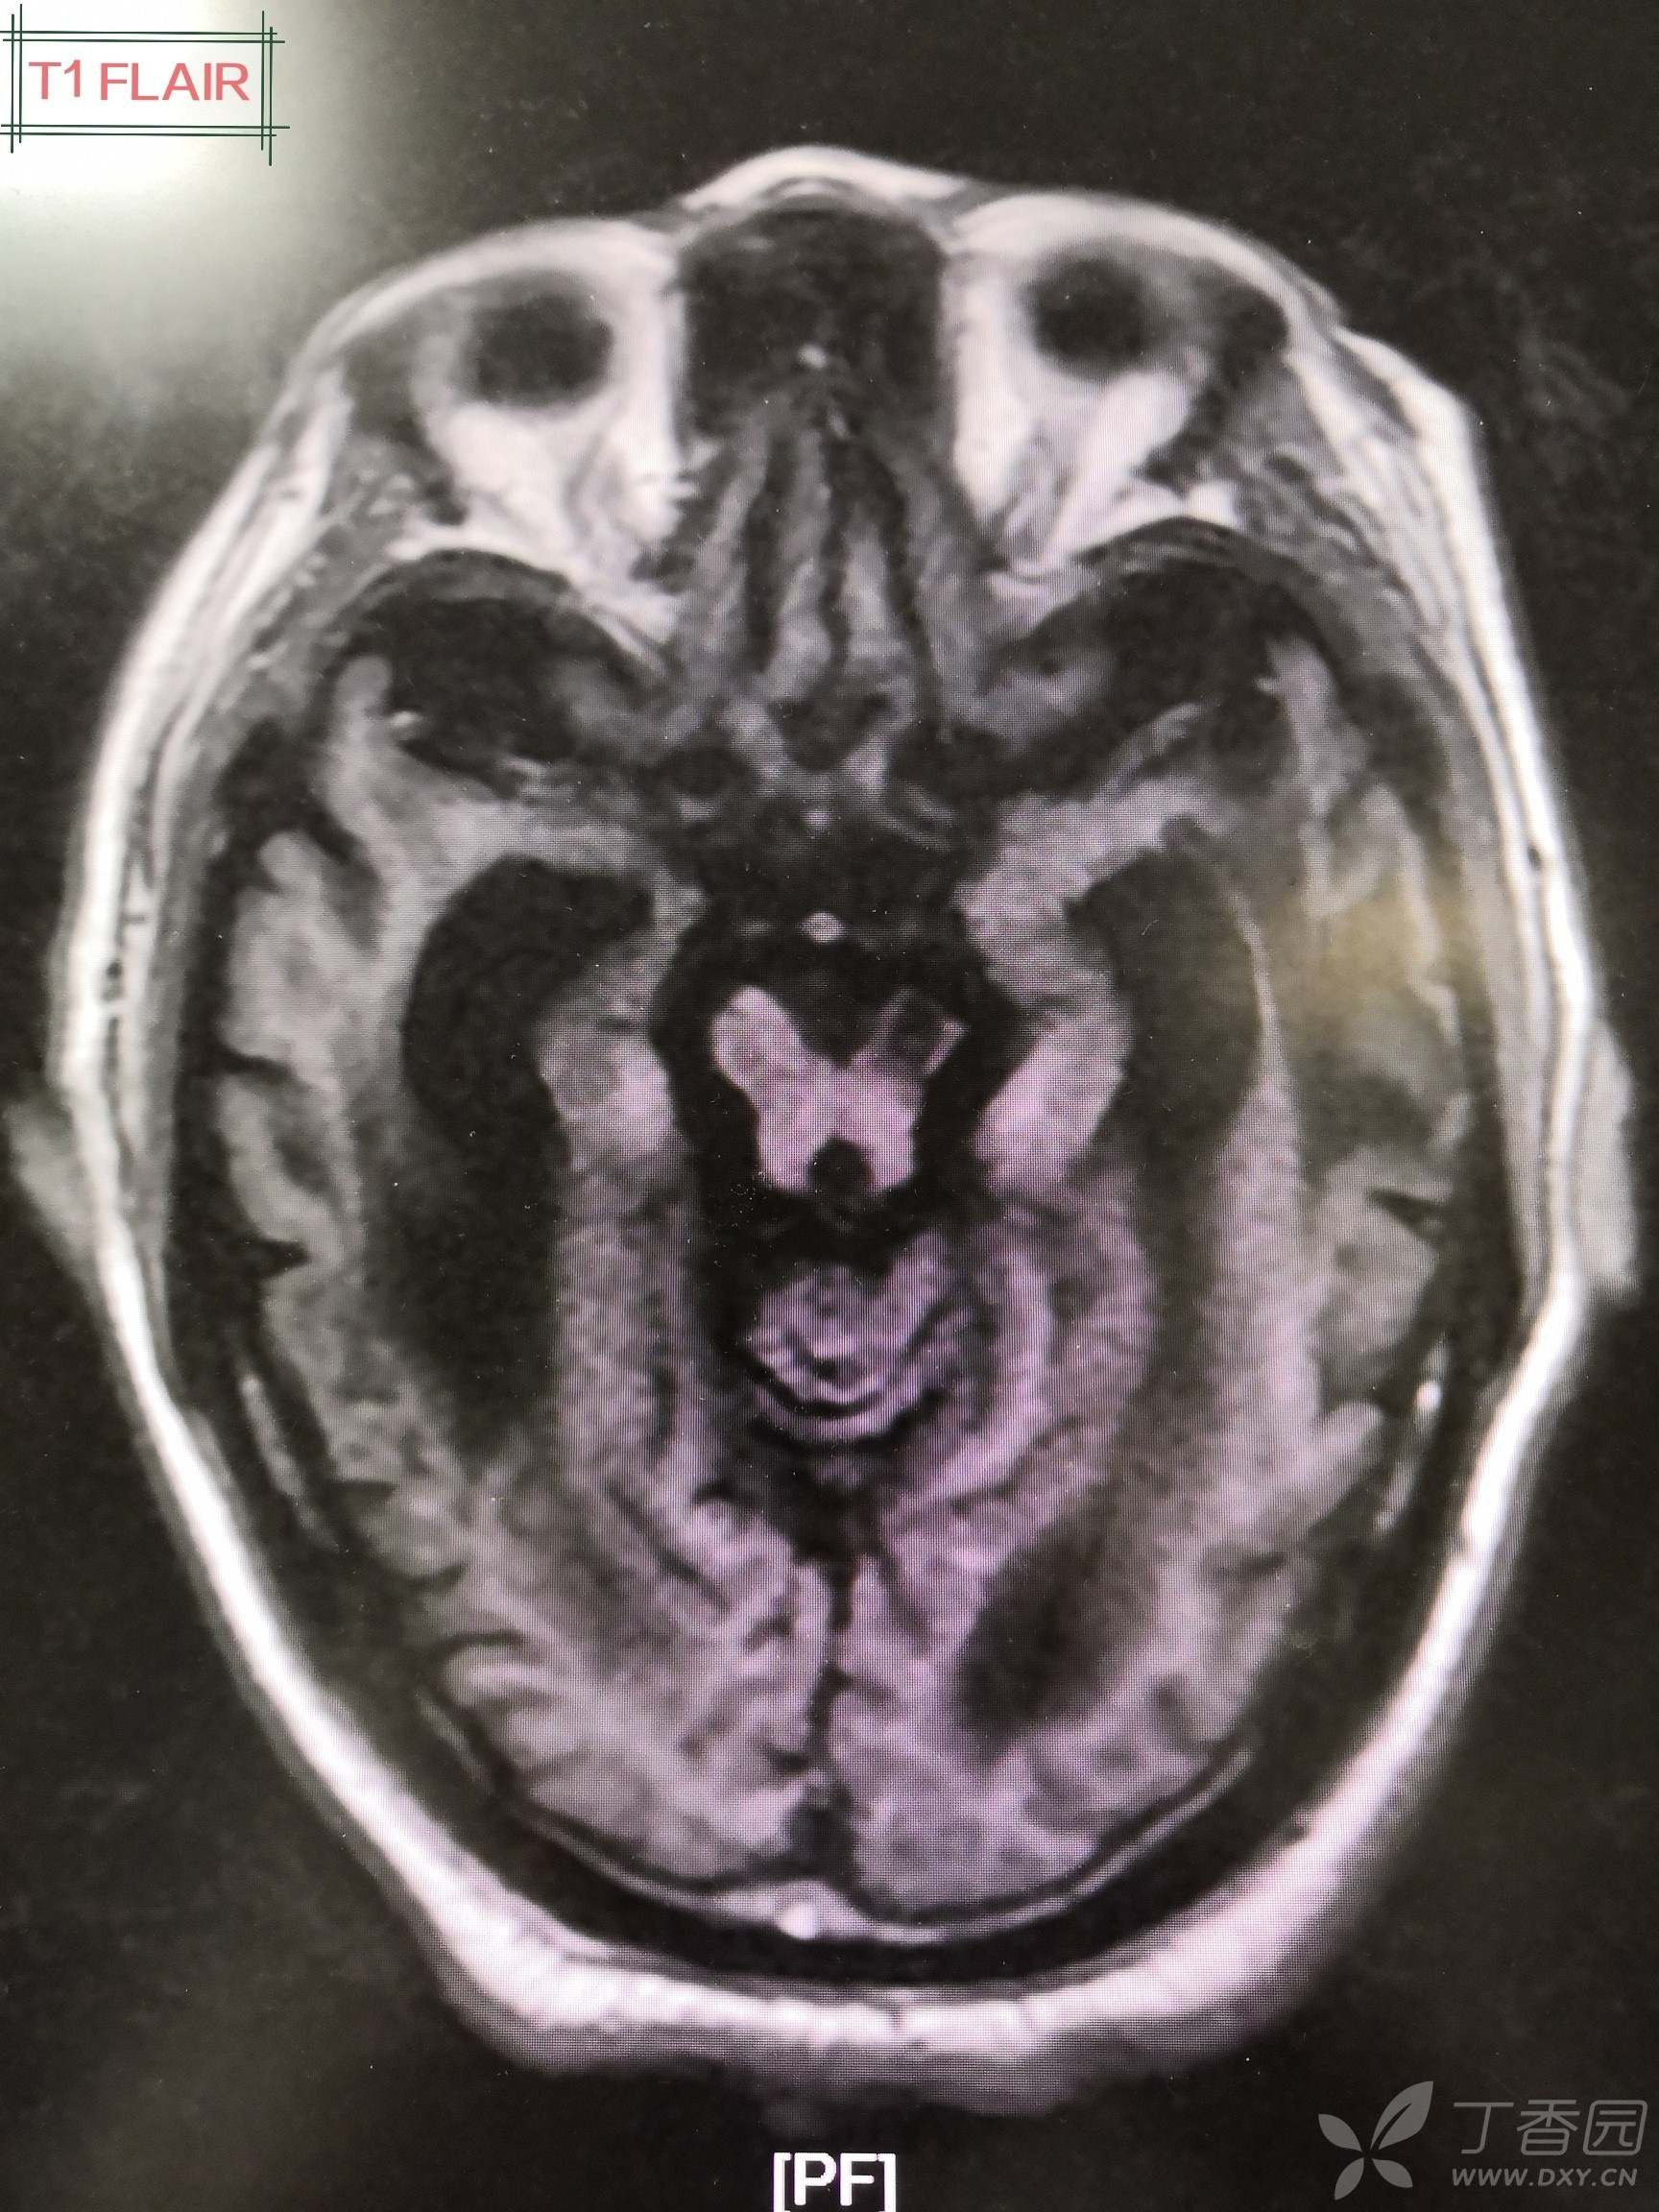

会诊意见:头颅磁共振结果回报后再次请神经外科及影像科会诊:左顶叶多发类圆形病灶DWI呈高信号,长T1长T2信号,FLAIR呈等信号,MRI增强扫描环形强化。左侧顶叶类圆形占位性病变符合脑脓肿影像学表现,考虑脑脓肿,建议抗感染基础上外科干预,侧脑室穿刺引流+冲洗,但基础疾病多,预后差。